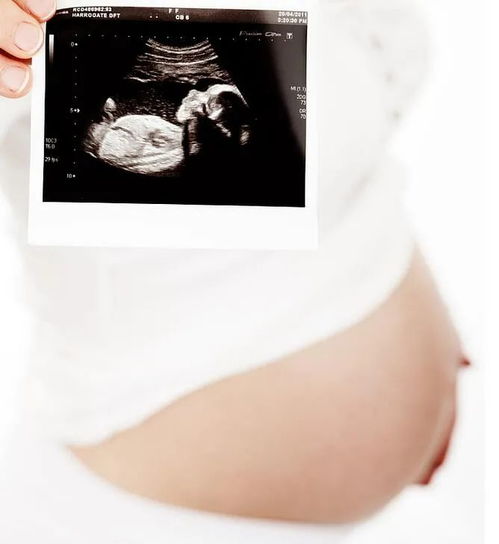

在孕期,B超检查是监测胎儿发育状况的重要手段之一。特别是在24周左右,进行系统B超检查对于了解胎儿的整体健康状况和发育情况具有重要意义。

24周是孕期的一个重要阶段,此时胎儿已经发育到一定程度,器官结构逐渐完善,系统B超可以更全面地评估胎儿的生长发育情况。通过系统B超,医生可以观察胎儿的各个器官、四肢、头部等部位,及时发现潜在的问题。

系统B超是孕期24周的重要检查项目,通过系统B超可以全面了解胎儿的生长发育情况,及时发现潜在问题。孕妇应重视系统B超检查,按照医生的建议进行预约和检查,确保胎儿的健康发育。